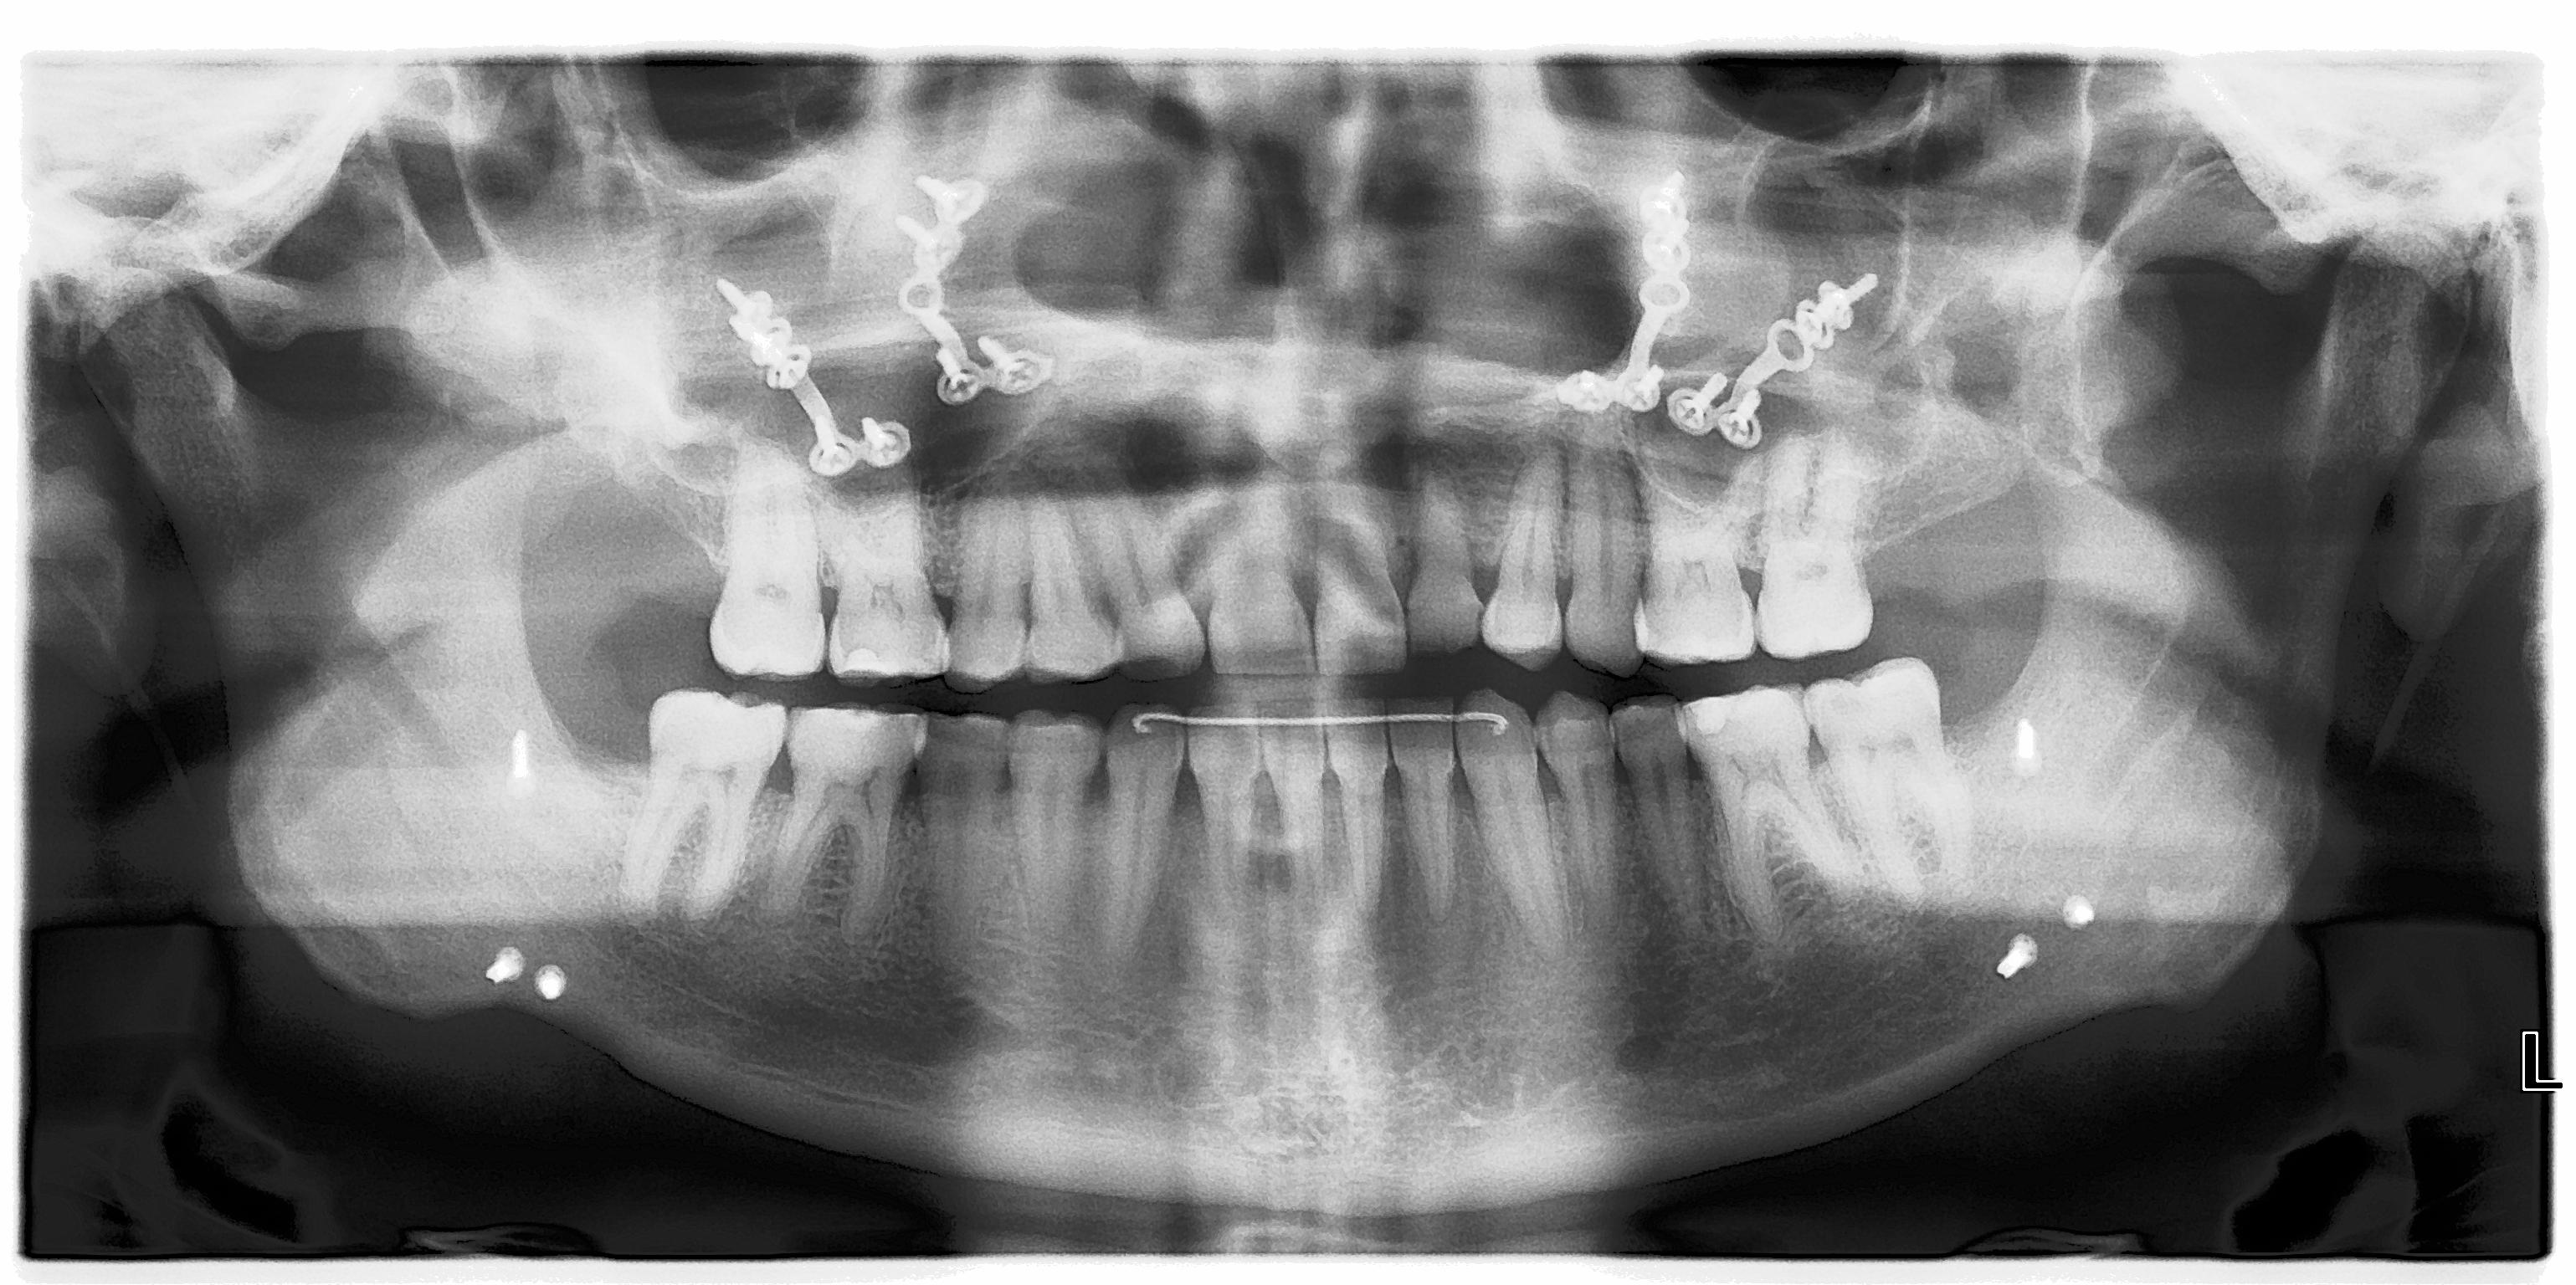

Jaw Surgery damages your body and frequently causes long-term problems. You should avoid it.

Jaw surgery is presented as safe, but this is simply not true.

It often causes side effects that outweigh any cosmetic or functional gains.